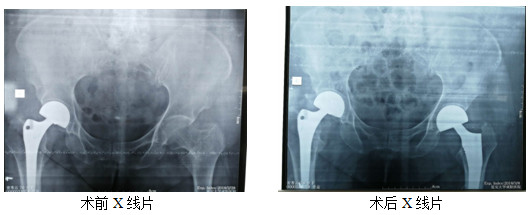

近日,患者姜某某,女性,76岁,因摔伤致左侧髋部疼痛4小时入院,行拍片,诊断:左侧粗隆间粉碎骨折。因患者年龄偏大,体重较重,右侧于入院前两年在外院行关节置换手术。家属慕名来骨科一病区就诊。入院后,立即给予对症处理,完善各项术前评估,并于伤后第3天行手术治疗。过去术后一个半月左右才允许患者下床活动。现在患者麻醉清醒后就开始患肢活动,术后3天,逐渐在下肢助行器的辅助下进行完全负重活动。对比上次外院手术、康复情况及就医体验,患者及家属表示非常满意。

骨科一病区在创伤、关节、骨病、脊柱、足踝肩肘外科等骨科领域的治疗方面具有丰富的临床经验。可开展各种复杂四肢骨折及关节内骨折、脱位的手法及手术治疗;全髋关节及全膝关节置换术;骨不连、急慢性骨髓炎、关节炎的手术治疗。脊柱骨折脱位并截瘫的手术治疗。颈、胸、腰椎间盘突出症、椎管狭窄症的手术治疗。四肢骨肿瘤的手术治疗。近年来,科室开展了复杂髋关节病变全髋关节置换术、椎管内占位性病变的手术治疗 、骨关节炎的保髋、保膝治疗等,均具市内先进水平。